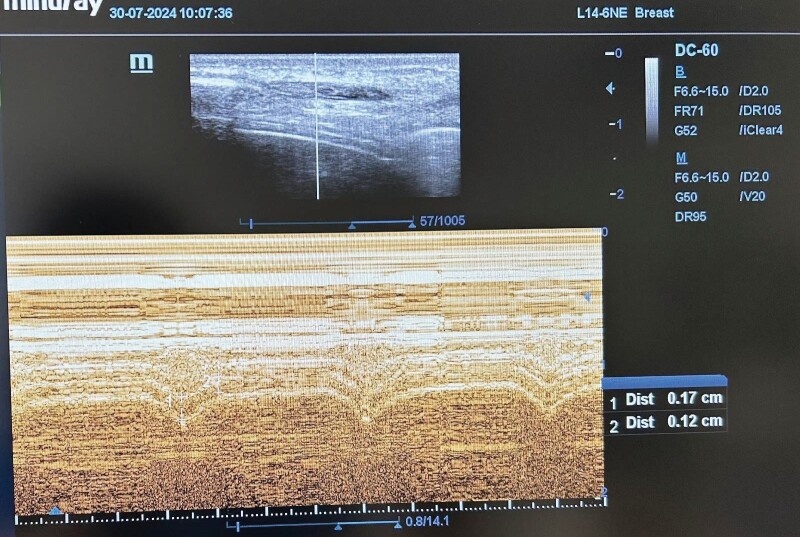

Materials and methods: The lung parenchyma and diaphragm of 50 patients were investigated using ultrasound (USG) on day 1, 5, and 10 of MV therapy.

Result: Mean age of the patients was 64.90 ± 15.96 years. Mean MV duration was 90.18 ± 21.09 days. Mean thickening fraction (TFdi) on day 1, 5, and 10 was 40.77 ± 15.42, 39.85 ± 16.85, and 43.57 ± 19.10, respectively. Mean diaphragm amplitude on day 1, 5, and 10 was 1.70 ± 0.74, 1.76 ± 0.74, and 1.70 ± 0.71, respectively. Mean diaphragmatic thickness at the end of expiration (Tde) on day 1, 5, and 10 was 0.18 ± 0.08, 0.17 ± 0.06, and 0.16 ± 0.05, respectively. There was no significant change between measurement days by TFdi, diaphragmatic amplitude (DA), and Tde values. On admission, TFdi was less than 20% in 8% of the patients, DA was less than 1 cm in 12%, and Tfde was less than 0.2 cm in 52%. There was no significant difference by the TFdi, DA and lung ultrasonography (LUS) scores of the non-surviving and surviving patients. An analysis of imaging results and LUS scores indicated that LUS values were measured higher in patients with infiltration on chest radiography. In addition, LUS scores significantly decreased from day 1 to day 5 and day 10, and from day 5 to day 10.